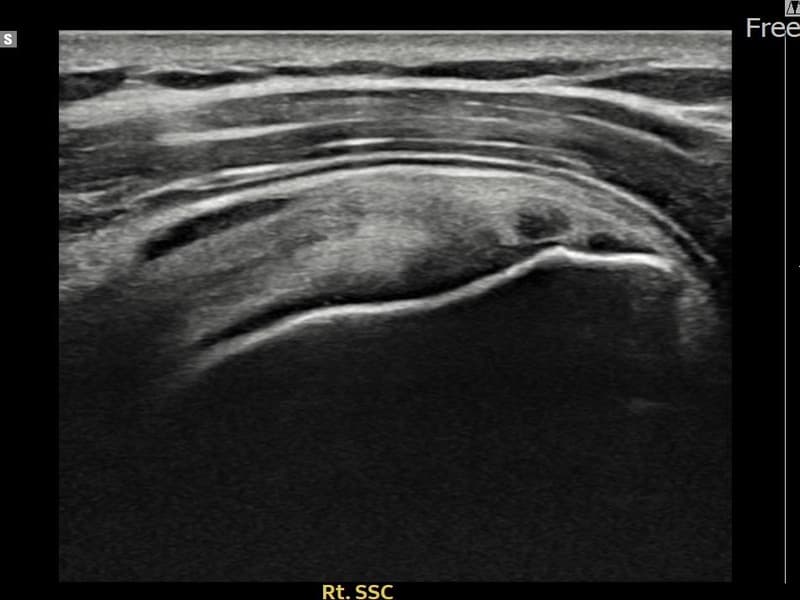

超声确认右侧 견갑하근건 部分撕裂(8mm × 3mm (肌腱厚度约32%缺损))。缩小缝合术后肌腱连续性恢复,患者回归正常生活。

术前

术前超声确认右侧 견갑하근건 部分撕裂,右侧冈上肌腱回声不连续伴肌腱缺损(8mm × 3mm (肌腱厚度约32%缺损))。术后超声显示撕裂部位充满再生组织,肌腱连续性恢复,回声模式正常化。

该患者持续肩痛。详细超声检查确认右侧 견갑하근건 部分撕裂(缺损:8mm × 3mm (肌腱厚度约32%缺损))。在超声引导下实施非手术缩小缝合术。术后佩戴支具约4-6周,随后进行分阶段康复锻炼。随访超声确认肌腱连续性恢复、结构稳定,患者顺利回归日常生活。